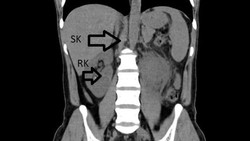

Pria 31 Tahun Niat Berobat gegara ISK Parah, Dokter Malah Temukan Ginjal Ketiga